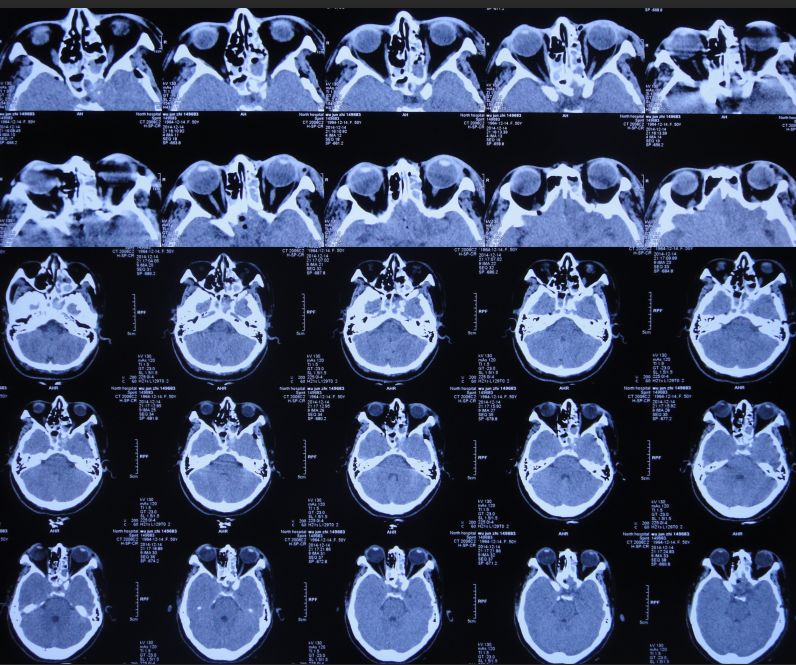

2015年8月7日,患者入院时表现(图16):神志清楚,坐起低头后感左鼻孔湿润、有液体流出,咽喉部稍发痒、疼痛,常有异物感,查体合作。左侧额部可见一长*宽约5*5cm的L形手术刀口,愈合良好。右侧额部可见一长约3cm手术瘢痕,结痂未脱落。右侧眼睑正常,左侧眼睑下垂,无眼球突出、内陷或斜视;双侧瞳孔不等大,右侧瞳孔约3.0mm,左侧瞳孔约6mm;右侧瞳孔对光反射正常,左侧瞳孔对光反射消失;右侧视力正常,左眼视力丧失。左侧下肢肌力3级-,右侧下肢肌力3级,双上肢肌力5级。肌张力:双侧肢体肌张力基本正常。

入院后第1天即2015年8月8日,复查头CT头:脑脊液蝶窦瘘征象。脑室扩张,双侧额叶片状密度减低,左侧额叶软化灶形成;脑沟、裂变浅;鞍上池及右侧脑室前角积气(图17)。

图17:2015年8月8日头CT:脑室扩张,鞍上池及右脑室前角积气